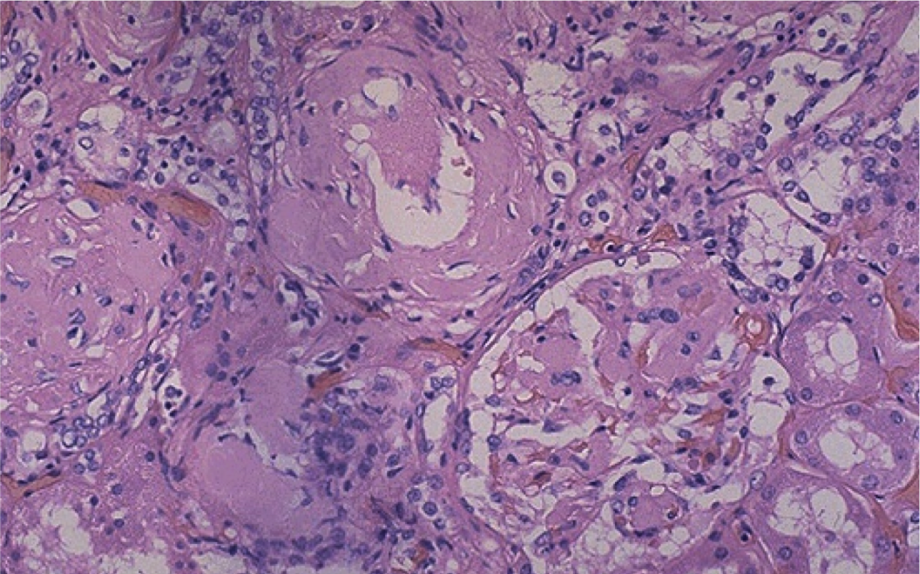

Амилоид состоит из глобулярных и фибриллярных белков, которые тесно переплетаются с полисахаридами. Незначительное отложение амилоида в железистых тканях, строме паренхиматозных органов, стенках кровеносных сосудов не вызывает каких-либо клинических симптомов. Но при значительных амилоидных отложениях в органах происходят выраженные макроскопические изменения. Объем пораженного органа увеличивается, его ткани приобретают восковой или сальный блеск. В дальнейшем развивается атрофия органа с формированием функциональной недостаточности.

Для окончательной диагностики необходимо произвести пункционную биопсию пораженных тканей (слизистой оболочки прямой кишки, желудка, лимфатических узлов; десен; почек) с последующим гистологическим исследованием полученного материала. Обнаружение в исследуемом образце амилоидных фибрилл будет подтверждением диагноза.